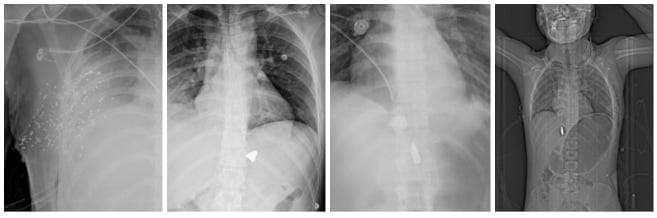

2. Chest and lungs

Several patients suffered penetrating chest trauma. Recurrent findings included:

- Pneumothorax (air compressing the lung)

- Hemothorax (blood filling the chest cavity)

- Subcutaneous air from open wounds

- Chest tubes inserted as emergency intervention

Untreated, such injuries can be fatal within minutes. Some scans suggested projectiles may have traversed the chest, potentially damaging multiple organs.

B) 7.62×39mm high-velocity bullets

10 cases

These injuries were consistent with ammunition fired from Kalashnikov-pattern assault rifles such as the AK-47 and its variants (including AKM, Type 56, and locally produced derivatives).

Radiological features included:

- Large deformed metal projectiles

- Deep penetration

- Severe bone fragmentation

- Projectiles lodged inside the body

- Chest trauma with pneumothorax

- One case of brain injury with high mortality risk

- One case of a neck wound with tracheal displacement

- Several suspected femoral artery injuries

Among all weapon categories, the 7.62mm cases showed the highest tissue destruction and lethality potential.